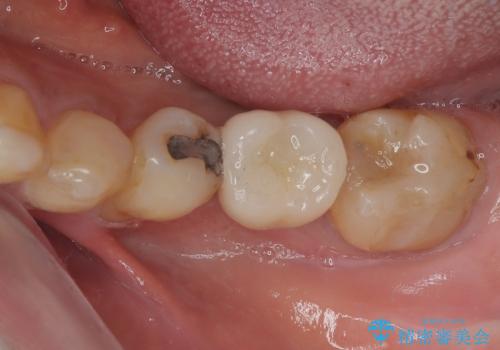

下顎大臼歯の抜歯即時埋入インプラント治療では、複数ある歯根のうち、後方の歯根部にインプラントを埋入することで一般的であり、今回破折して骨吸収が著しいのは前方の歯根であったため、事前に仮歯を用意した上で、抜歯即時埋入インプラントによる補綴治療を行うこととしました。

来院されるまではインプラント治療を躊躇されていましたが、抜歯即時埋入により、単回の外科処置で治療が終えられることのメリットを理解され、インプラントによる補綴治療を行いました。

スムーズに治療を終えることができました。